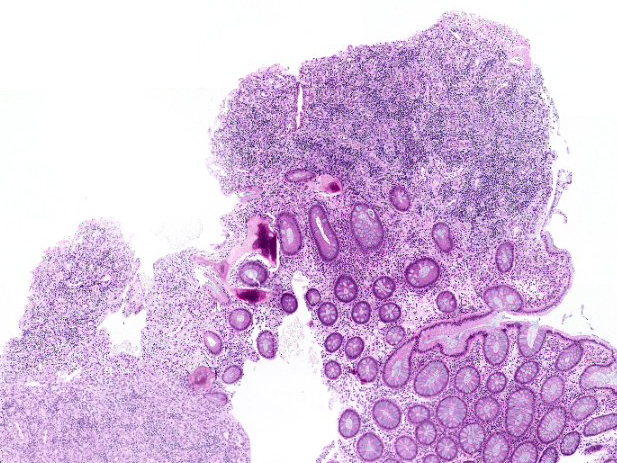

H&E sections of the specimen demonstrate a polypoid projection of the mucosa with focal architectural distortion in form of irregularly dilated and branched crypts, lined by columnar epithelium without dysplasia. Large parts of the polyp were composed of granulation tissue with mixed inflammatory infiltrate, rich vascular network and fibroblastic stroma. Adjacent to the colonic crypts small areas of mineralized woven bone formation with vital osteocytes were identified (Panels B-C).

Osseous metaplasia has been observed in various types of tissue, associated with neoplastic as well as non-neoplastic conditions. Benign lesions often showed active chronic inflammation and ulceration alongside areas of osseous metaplasia, suggesting that persistent inflammation may play a role in osteogenic stimulation under the influence of transcription factors, such as bone morphogenic proteins (BMPs). This concept is underpinned by our case, which shows foci of bone formation within an inflammatory pseudopolyp that occurred against the background of chronic inflammatory bowel disease.